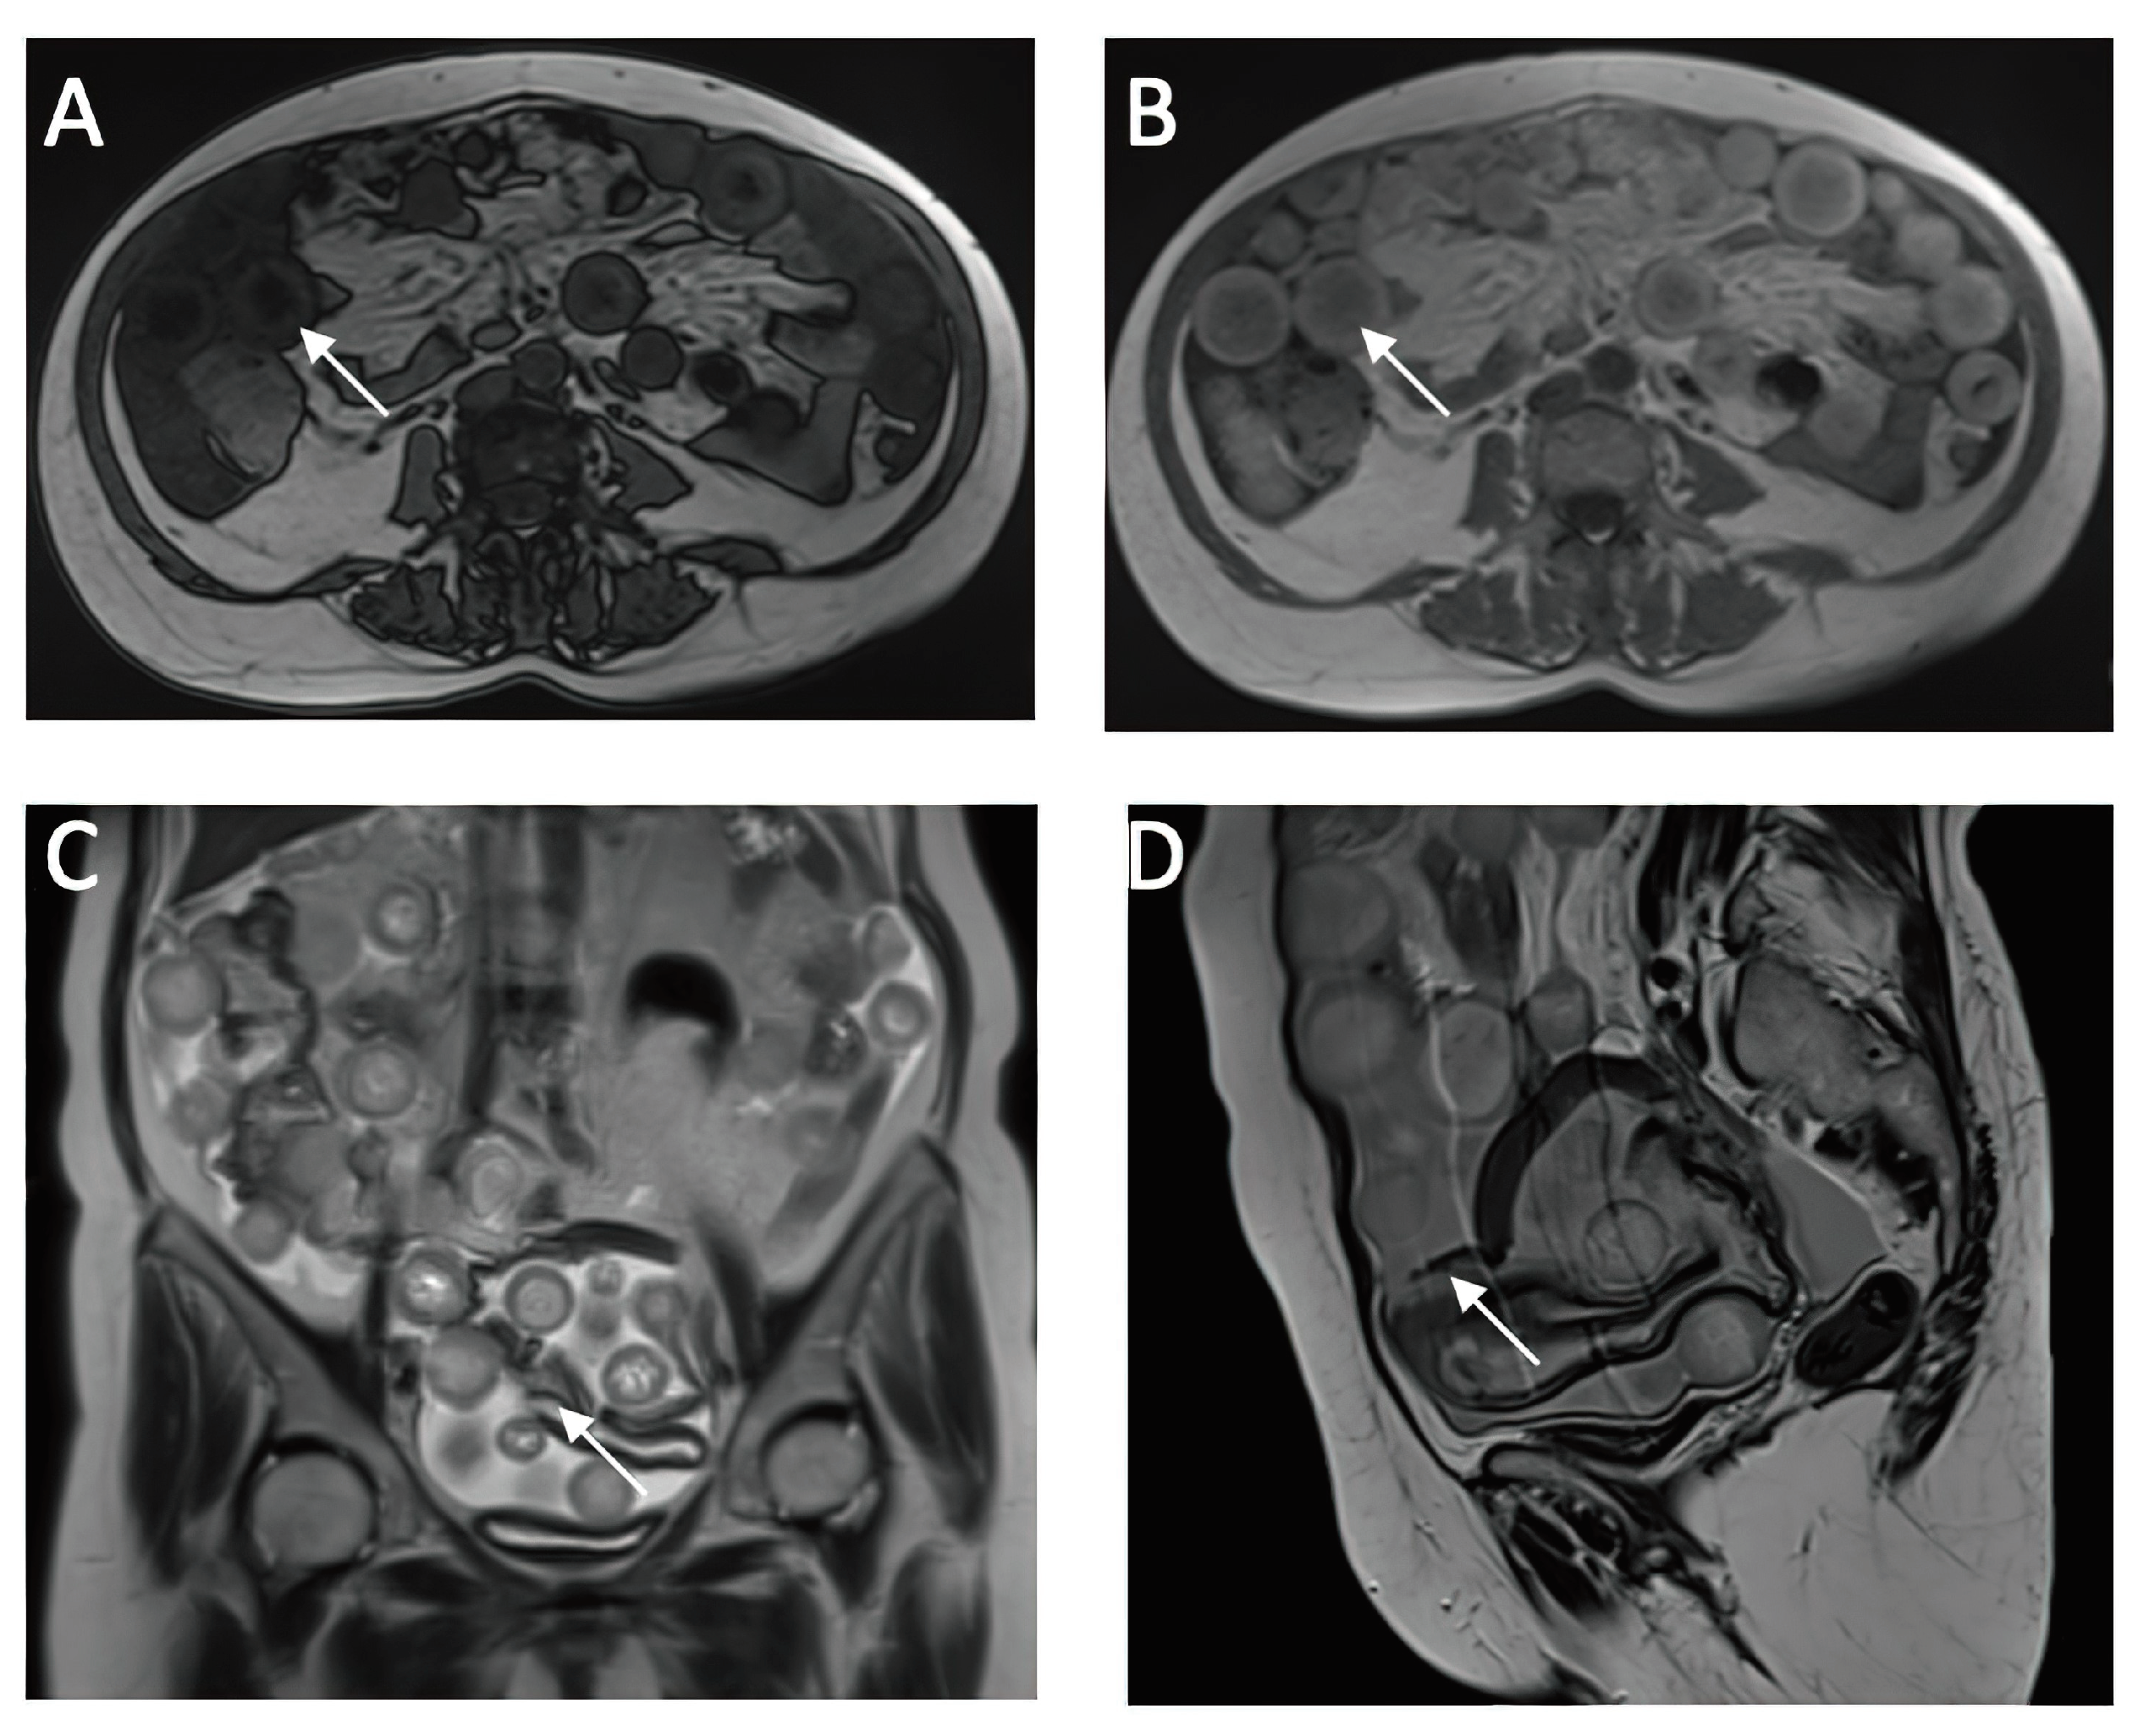

A CT investigation of the abdomen and pelvis was requested and performed. Radiology noted the presence of ascites in moderate amount, together with numerous round nodular lesions of varying sizes (between 1.5-4 cm), with no contrast uptake; the lesions were randomly distributed, with a slight prevalence for the pelvic region. However, a serpiginous lesion with intense contrast uptake was observed within the left ovary (Figure 1), leading the radiologist to falsely raise the suspicion of ovarian carcinoma with peritoneal carcinomatosis. The patient was hospitalized for additional investigations and medical treatment. After several days, an abdominal and pelvic MRI was also performed (Figure 2). Several ‘floating round bodies’ were observed throughout the whole peritoneum; the ‘floating bodies’ showed signal drop on the out-of-phase sequences suggesting fatty components. When analyzing the pelvic images, a ruptured cyst was observed across the right ovary. The diagnosis of ruptured ovarian teratoma was made and the patient underwent surgery. Left adnexectomy with peritoneal lavage and lysis of entero-enteric adhesions was performed. During the laparotomy, the peritoneal cavity was opened revealing a moderate amount of peritoneal fluid. A sample was then collected for cytologic examination. Macroscopically, the uterus had a normal appearance, with unremarkable right adnexa and left fallopian tube. As for the left ovary, a cystic mass with ruptured wall was observed. The cyst contained multiple well defined round lesions with fatty content, some of which were disseminated throughout the peritoneal cavity. The surgical findings are depicted in Figure 3.

Figure 2. Cross-Sectional MRI Analysis of Abdominal and Pelvic Organs (a,b) in-phase and op-phase images showing signal dropout on the op phase, suggesting fat content of the sphere (c,d) ruptured cyst wall which is hypointense on the T2w sequence